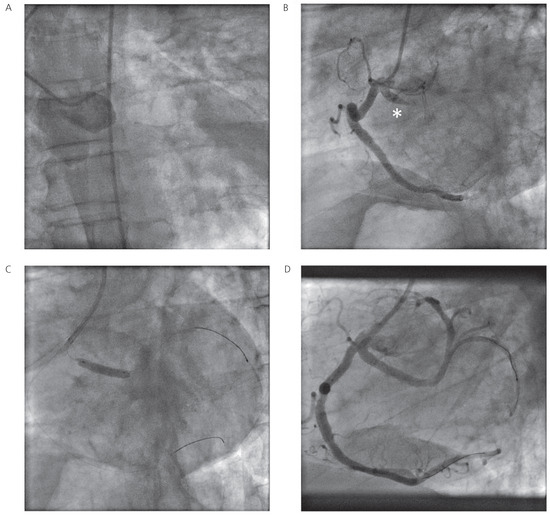

Myocardial Infarction in a Patient with a Single Coronary Artery

by Marcus Mutschelknauss, Peter T. Buser, Christoph Kaiser, Jean-Luc Crevoisier and Michael J. Zellweger

Cardiovasc. Med. 2011, 14(6), 195; https://doi.org/10.4414/cvm.2011.01596 - 29 Jun 2011

A 56-year-old male patient was admitted because of ST-elevation myocardial infarction (STEMI) with STelevations in lead I and aVL [...] Full article